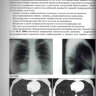

Примеры страниц из книги "Заключения в торакальной компьютерной томографии. Симптом, синдром, диагноз" - А. А. Сперанская